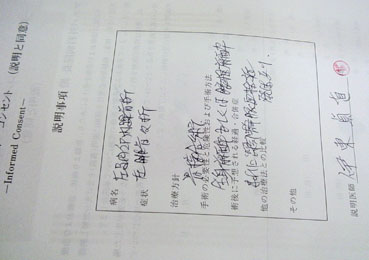

| 骨折の手術は2週間後の10月3日に行われた。 | |||||||||

■そしてバンジャは足の手術をする(2006/10/3)

■バンジャの足手術終わる(2006/10/3)